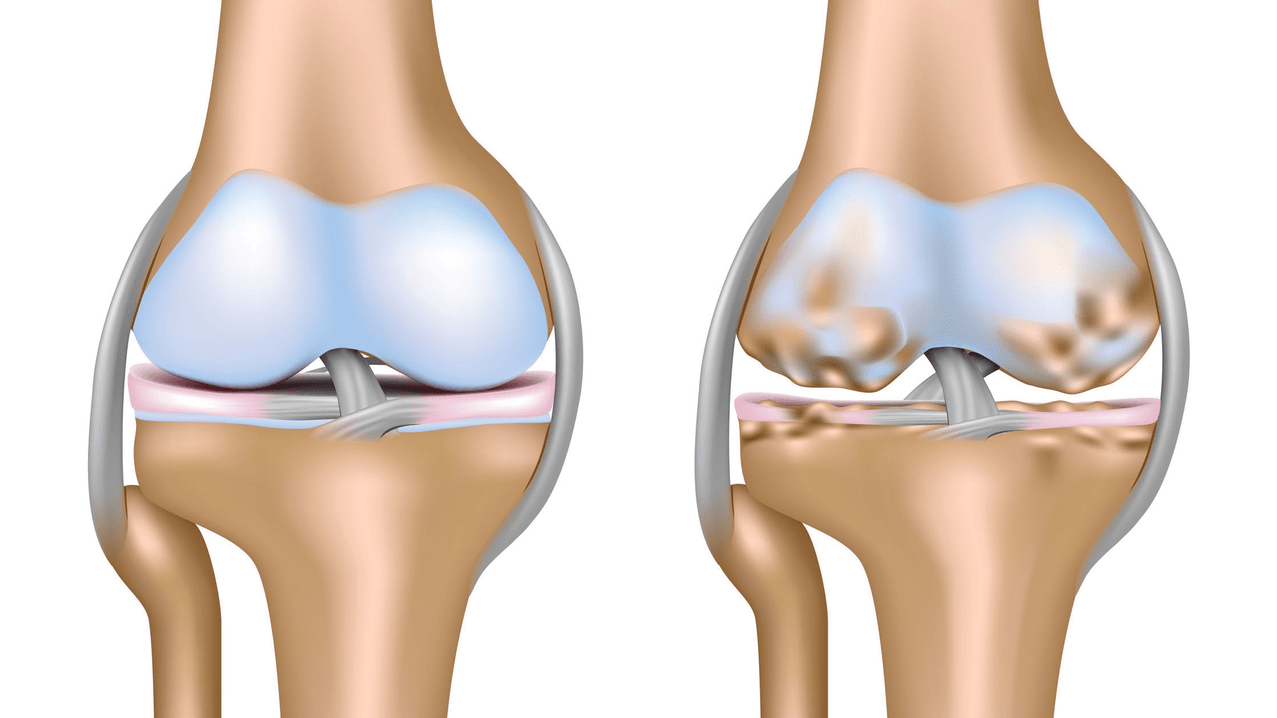

Artrose van het kniegewricht (gonartrose) is een progressieve chronische ziekte van de kniegewrichten met schade, verdunning en vernietiging van het kraakbeenachtige deel (gewrichtsoppervlakken van het dijbeen en het scheenbeen), evenals schade aan het subchondrale bot. Uit onderzoek (arthroscopie en MRI) is gebleken dat naast schade aan het gewrichtskraakbeen ook de menisci en het synoviale membraan bij het proces betrokken zijn. Gonartrose is een van de meest voorkomende orthopedische pathologieën. Er zijn synoniemen: artrose (OA), vervormende artrose. De ziekte is een belangrijk sociaal-economisch probleem, omdat zij wijdverspreid is en de levenskwaliteit van patiënten aanzienlijk verslechtert als gevolg van aanhoudende pijn, en bovendien een oorzaak wordt van hoge invaliditeit.

Tot het midden van de jaren tachtig van de vorige eeuw bestond er geen uniforme definitie van de ziekte. Pas in 1995 karakteriseerde de osteoartritiscommissie van het American College of Rheumatology de ziekte als het resultaat van mechanische en biologische factoren die leidden tot een onevenwicht tussen de processen van afbraak en synthese van de extracellulaire matrix van gewrichtskraakbeen. Als gevolg hiervan treden vezeldesintegratie en degeneratie op, worden scheuren, osteosclerose en verdichting van de corticale laag van het subchondrale bot gevormd, groeien osteofyten en worden subchondrale cysten gevormd.

- Gewrichtskraakbeen wordt voortdurend vernietigd en vernieuwd; Normaal gesproken zijn deze processen in evenwicht. Met het ouder worden vertraagt de vernieuwing van het kraakbeen en begint de vernietiging de overhand te krijgen, wat het proces van afbraak of degeneratie wordt genoemd. Het gewicht van een persoon speelt een belangrijke rol, aangezien we met een massa van 70 kg in 20 stappen 700 kg op elk been dragen (70 kg x 10 stappen), en met een massa van 120 kg al 1200 kg op elk been dragen. Daarom verslijt zwak kraakbeen veel sneller;

Bij artrose (osteoartrose) worden, naast de progressieve vernietiging van kraakbeen, verlies van de elasticiteit en schokabsorberende eigenschappen, botten geleidelijk bij het proces betrokken. Onder belasting verschijnen scherpe randen (exostoses), die ten onrechte als "zoutafzettingen" worden beschouwd - bij klassieke artrose vindt geen zoutafzetting plaats. Naarmate de artrose vordert, blijft het het kraakbeen ‘opeten’. Dan raakt het bot vervormd, vormen zich daar cysten, worden alle structuren van het gewricht aangetast en wordt het been gebogen.

De eerste fase van de ziekte wordt gekenmerkt door primaire veranderingen in het hyaliene kraakbeen. Botstructuren worden niet aangetast. De bloedtoevoer in intraossale bloedvaten en haarvaten is verstoord. Het oppervlak van het kraakbeen wordt droog en verliest zijn gladheid. Als de ziekte gepaard gaat met constante gespannen synovitis, ontwikkelt zich een Baker-cyste (herniale uitsteeksel van de gewrichtscapsule van het popliteale gebied). Na aanzienlijke belasting van het gewricht treedt doffe pijn op. Er kan een lichte zwelling optreden die na rust verdwijnt. Er is geen vervorming.

Gonartrose, stadium II

In de tweede fase wordt de kraakbeenlaag aanzienlijk dunner en is deze op sommige plaatsen volledig afwezig. Osteofyten verschijnen langs de randen van de gewrichtsoppervlakken. De kwalitatieve en kwantitatieve kenmerken van de synoviale vloeistof van het gewricht veranderen: het wordt dikker, stroperiger, wat leidt tot een verslechtering van de voedings- en smerende eigenschappen. De pijn is langduriger en intenser, en er is vaak een knarsend geluid te horen bij beweging. Er is sprake van een lichte tot matige bewegingsbeperking en lichte vervorming van het gewricht. Het nemen van pijnstillers helpt de pijn te verlichten.

Gonartrose, stadium III

Gebrek aan kraakbeen in de meest getroffen gebieden, ernstige sclerose (verharding) van het bot, veel osteofyten en een scherpe vernauwing of afwezigheid van de gewrichtsspleet. De pijn is bijna constant, het lopen is verminderd. De mobiliteit is sterk beperkt en gewrichtsvervorming is merkbaar. NSAID's, fysiotherapie en andere standaardmethoden voor de behandeling van knieartrose zijn niet effectief.